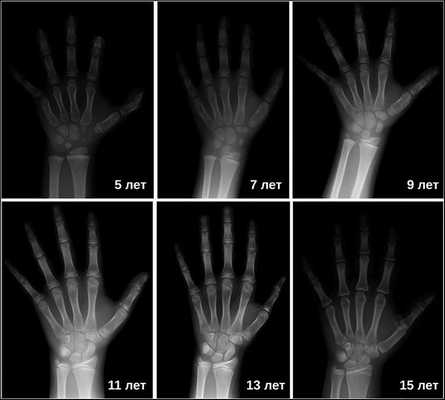

- рентген кисти для определения костного возраста;

Рентгенография турецкого седла выявляет его детскую форму («стоячий овал») и широкую (т. н. ювенильную) спинку. При увеличении размеров турецкого седла и наличии участков обызвествления, в первую очередь, следует думать об опухоли. Рентгенография лучезапястных суставов и кистей позволяет определить рентгенологический («костный») возраст. При гипофизарном нанизме отмечается значительное замедление процессов окостенения скелета.

Основной симптом — отставание в темпах линейного роста [2] . Такие дети вырастают менее чем на 4 см в год. Нарушение динамики роста будет заметно уже в первые месяцы жизни ребёнка. Если повреждение гипоталамуса или гипофиза возникло в более позднем возрасте, то отставание в росте будет отмечаться позднее. Также для детей с гипофизарным нанизмом характерно отставание костного (биологического) возраста от паспортного (фактического) более чем на 2-3 года.

Затем врачи определяют костный возраст. Сделать это можно с помощью рентгена или УЗИ запястья. В норме костный возраст может отставать или опережать паспортный на два года.